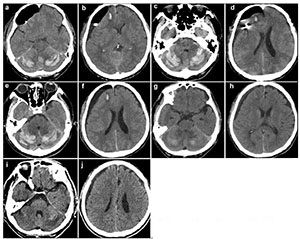

Anti-platelet therapy was suspected as a possible cause of the spontaneous occurrence of the right subdural hematoma. Preoperative coagulation parameters (prothrombin time, activated partial thromboplastin time, fibrinogen, thrombin time, and platelet count) were normal. The patient was too dysphoric to undergo surgery owing to increasing headache and confusion. Surgery was performed under general anesthesia with slight head rotation. Frontal and parietal burr-holes were drilled, followed by continuous subdural irrigation with tepid isotonic saline. The operation lasted 65 min. Perioperative blood pressure remained within the normal range. The drainage tube was connected to a closed collection system, which was fixed to the bed at the level of the patient's head. The patient's Glasgow Coma Score (GCS) improved from 12 to 15 postoperatively. A total of 220 mL, 190 mL, and 90 mL of cerebrospinal fluid (CSF) were drained from the subdural space at 24 h, 48 h, and 60 h, respectively. The patient suddenly developed nausea and vomiting, followed by deterioration of consciousness and stupor, 60 h after the evacuation. An urgent CT scan was performed, which demonstrated a significant hematoma in bilateral cerebellar hemispheres (diameter >4 cm) and a small hematoma in the frontal lobe (Figures 2a and 2b). At that time, the coagulation parameters in the blood were normal. In view of the patient's concurrent medical problems, with worsening respiratory function and poor prognosis, he was not deemed suitable for posterior fossa surgery. The patient was administered hyperosmolar therapy (250 mL of 20% mannitol every 6 h, 100 mL of 20% albumin per day), infection prophylaxis, and bed rest. The patient's GCS which was maintained at 11–12, gradually improved to 15 within 3 weeks. Repeat CT scans, which were performed 4, 7, 11, and 19 days after the operation, revealed that the bilateral cerebellar hemorrhage and frontal lobe hemorrhage had been largely absorbed (Figures 2c–2j). However, considering he had stent implantation history, it was risky to perform magnetic resonance imaging (MRI). Therefore, a preoperative CT angiography (CTA) was performed. CTA and CT venography revealed a hypoplastic right vertebral artery, and revealed dominant transverse sinus, mainly on the right side. The left side of intracranial segment of internal jugular vein and sigmoid sinus was totally undeveloped (Figure 3). The patient gradually recovered. He was discharged one month after surgery, without neurological complaints or deficits on examination.

|

| Figure 3 Preoperative computed tomography angiography (CTA; a, b) and computed tomography venography (CTV; c, d) of the brain of the patient. |

However, CSF loss alone does not cause RCH. Many neurosurgical centers have routinely performed extensive opening of the cisterns without observing an increase in the occurrence of RCH. The positioning of the head during surgery of the patient should also be considered in this case. Excessive head rotation coupled with hyperextension can lead to obstruction of the jugular vein[12]. Transverse sinuses that are of unequal size, which do not communicate at the torcula, may easily result in venous infarction with hemorrhage in patients[13]. Our patient had a totally undeveloped left intracranial segment of the internal jugular vein. The sigmoid sinus was at a greater risk of suffering occlusion of the cerebellar venous system when draining veins on the other side was compressed owing to head rotation. Quick clearance of the subdural hematoma coupled with the drainage of the excessive CSF could have rapidly reduced the supratentorial pressure. An increase in the transmural pressure between the supratentorial and subtentorial region could have subsequently shifted the cerebellum, possibly resulting in damage to the cerebellar draining veins, which in turn may have led to cerebellar hemorrhage.